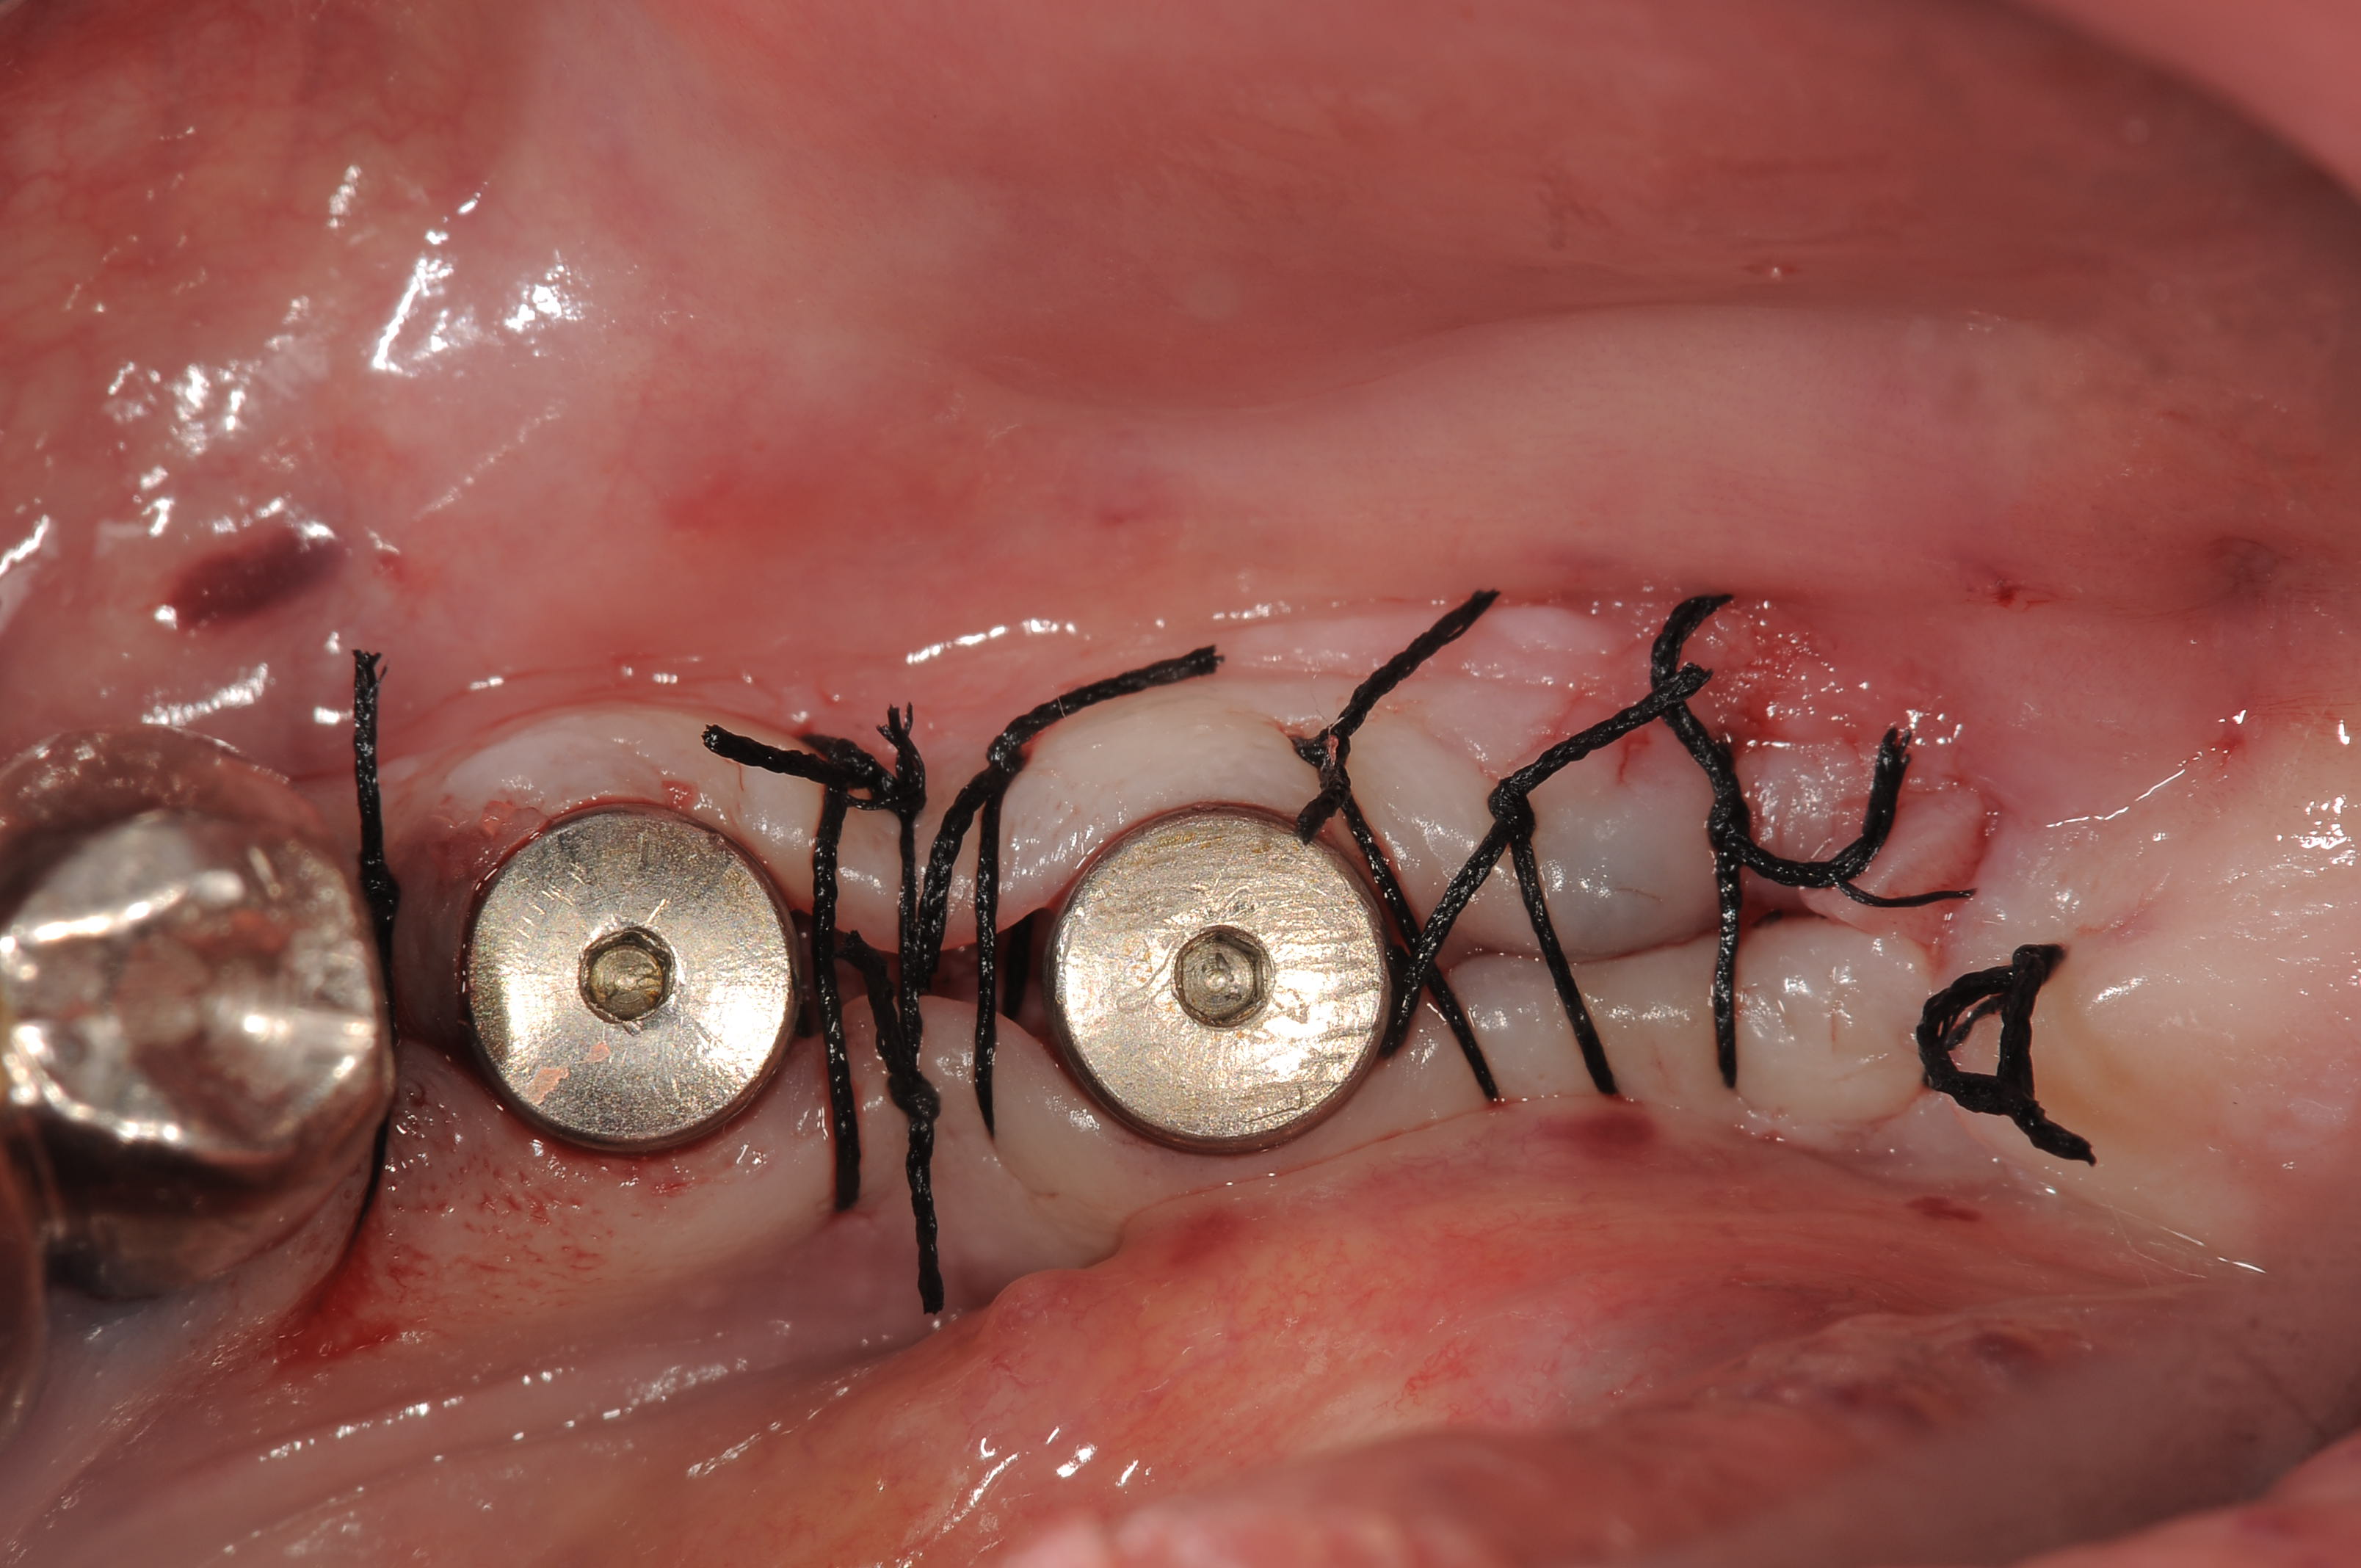

今日は、右下の56部位の成熟側へのサイブロンプロEXの埋入をしました。

5番部位の頬側の骨がやや陥凹していて足りませんでしたので、舌側の骨縁から自家骨を採取して移植しました。

付着歯肉、骨量ともに豊富で特に何も問題なく、固定も十分に取れました。

プラットフォームスイッチのアバットメントが使用できるように、やや深めに埋入し、プラットフォームスイッチ用のヒーリングアバットメントを装着しています。

5番頬側には、自家骨を移植しています。

埋入後の状態ですが、付着歯肉の量も十分で何も問題ありません。